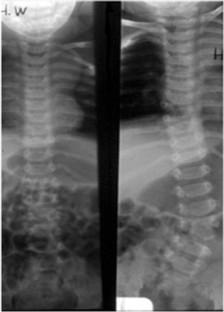

Fig. 1